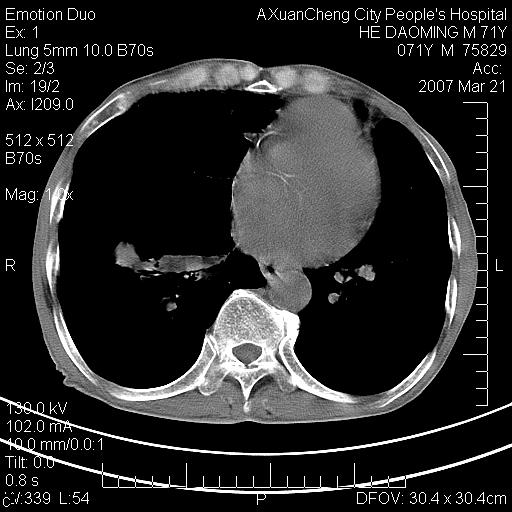

标题: CT7269:[原创] 咳嗽,咳痰,大家讨论右肺病变的部位 [打印本页]

标题: CT7269:[原创] 咳嗽,咳痰,大家讨论右肺病变的部位

1.慢支肺气肿 肺心病 肺大泡;2.叶间裂积液,前胸膜粘连

右侧相当于叶间软组织样密度ct值约50hu,请大家讨论是什么性者病变

右下肺大囊肿伴感染.肺气肿,肺大泡.

考虑:慢性支气管炎合并全小型肺气肿、肺大泡、间质纤维化、感染,右斜裂积液。

考虑慢支,肺气肿,肺大泡,间质纤维化;右侧斜裂液气胸考虑(可能因为肺大泡破裂破入斜裂所致).

考虑病变以右上中肺多发肺大泡为主并感染。请结合临床考虑慢支肺气肿,肺心病。

1双肺慢性支气管炎并全小叶型肺气肿肺大泡2间质性纤维化3右侧斜裂积液

考虑:慢性支气管炎合并右侧全小型肺气肿、肺大泡并感染、双肺间质纤维化,右斜裂积液。

考虑:慢性支气管炎合并右侧全小型肺气肿、肺大泡并感染、双肺间质纤维化,右斜裂积液。右侧斜裂液气胸考虑(可能因为肺大泡破裂破入斜裂所致).